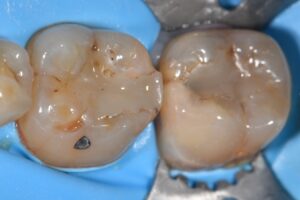

// DME using Omnimatrix and Matrix-in-matrix using #Omnimatrix/Garrison Dead Soft Bands